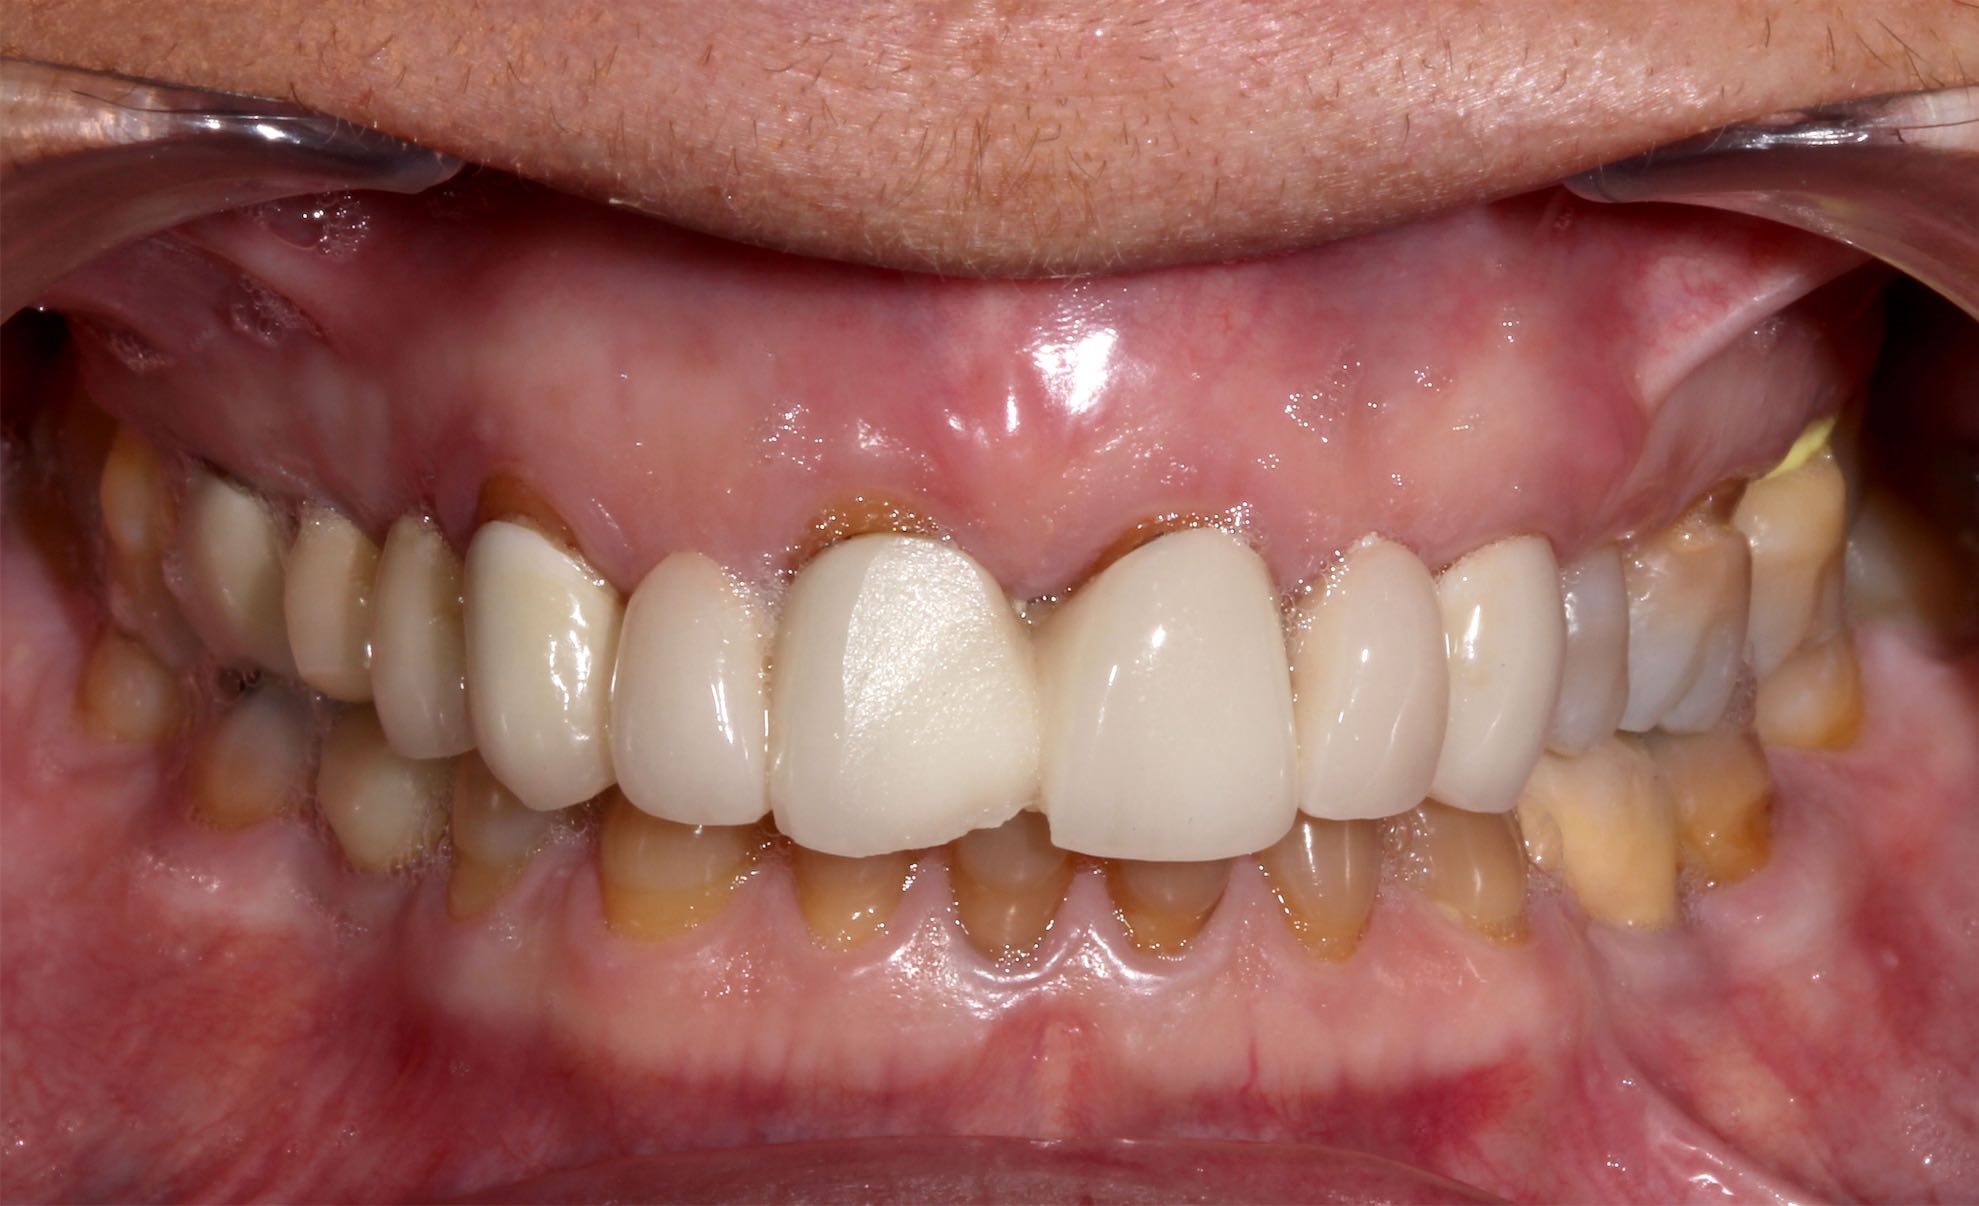

Odontología Estética. Coronas

BeforeAfter